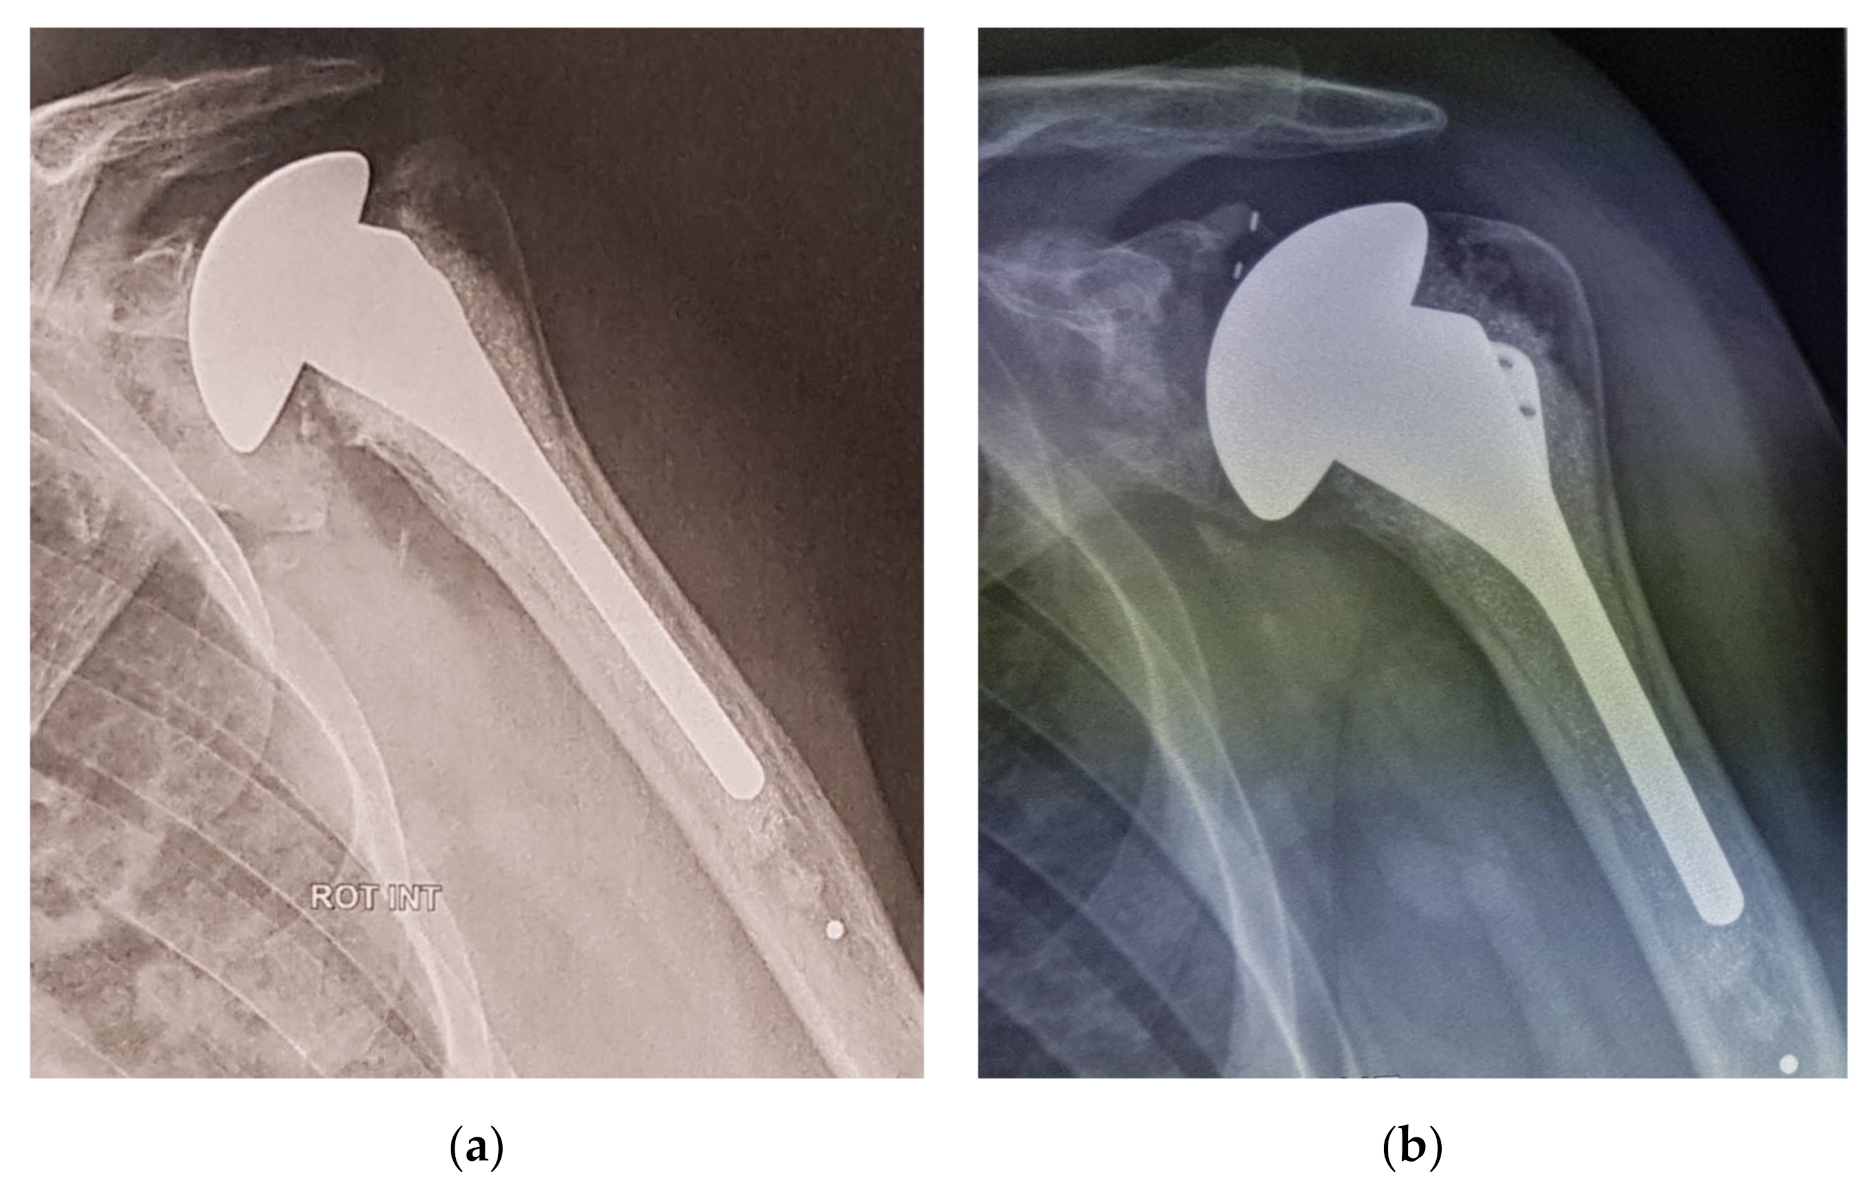

2.3. Hemiarthroplasty Group

4. Discussion